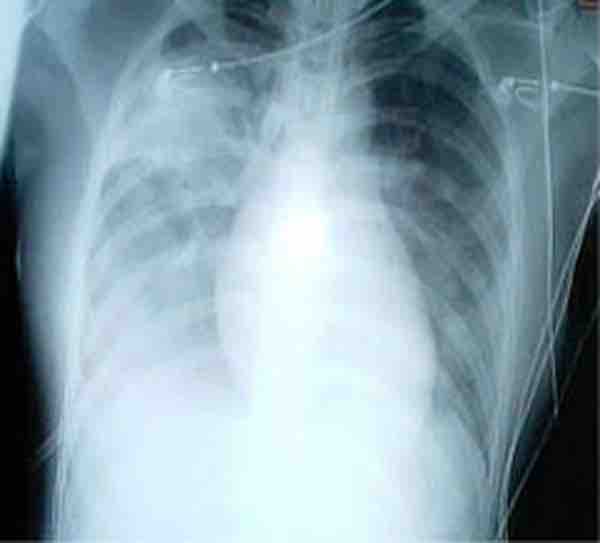

Medical importance of SARS

A chest x-ray showing increased opacity in both lungs, indicative of pneumonia, in a patient with SARS.